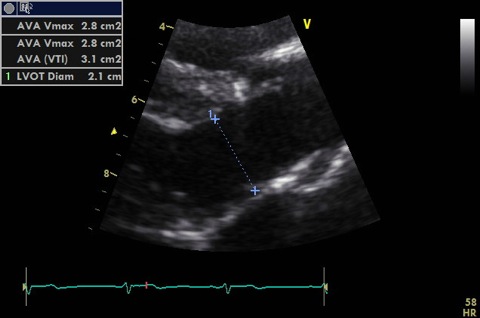

Measure in 2D:

- LVOT (up to 1 cm from aortic annulus - must PW at same point in A5C). Image should be shallow, narrow and zoomed to improve accuracy. Cross sectional area is calculated from this.